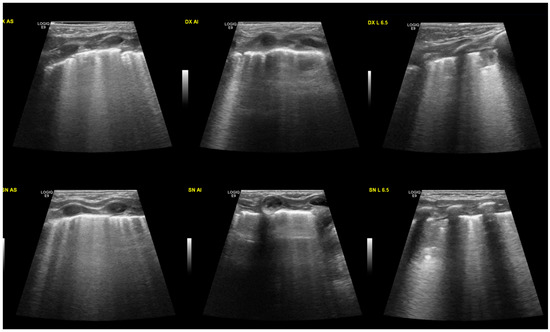

The areas of consolidation were in all cases bilateral and variously distributed in different areas of the lungs (Figure 2), with greater involvement of the right lung in four neonates (66%). In the two patients who required nCPAP, the consolidations were larger and more extensive. Three neonates also underwent chest radiography that showed “diffuse bilateral interstitial involvement” or “diffuse bilateral alveolar-interstitial involvement”.

Figure 2.

Sub-pleural extended consolidation. This patient has a more severe disease than the one presented in Figure 1. At the top of the image, the right lung is shown, divided into three areas: the upper anterior, lower anterior, and lateral. In the lower portion of the image, the left lung.